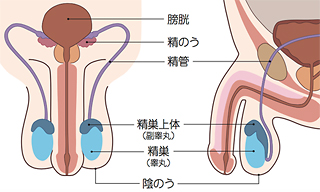

精巣はどんな臓器ですか?

精巣(せいそう)は、男性の股間の陰のう内部にある卵形をした臓器です。左右に1つずつあって、睾丸(こうがん)とも呼ばれています。

精巣には、精子と男性ホルモンを産生する働きがあり、生殖行為に関して重要な役割を担っています。